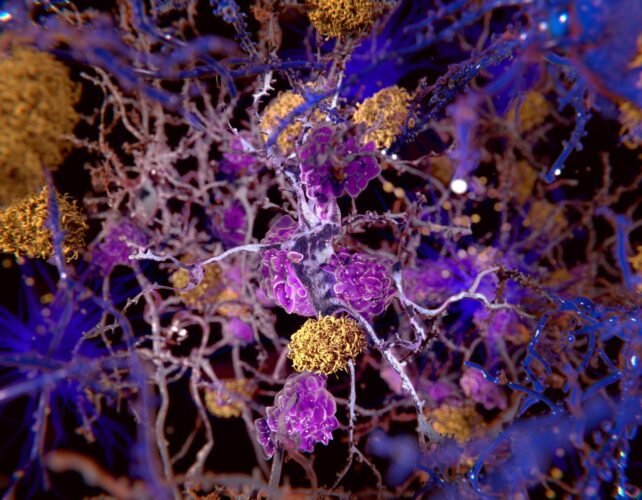

Our hypothesis posits that beta-amyloid is not an aberrant protein byproduct but rather a naturally occurring molecule integral to the brain’s immune defense mechanisms. Its presence is intended.

Upon experiencing brain injury or encountering bacterial invasion within the brain, beta-amyloid plays a crucial role in the brain’s comprehensive inflammatory response. This is precisely where the pathological process is believed to commence.

Due to significant structural resemblances between the lipid components of bacterial membranes and those of brain cells, beta-amyloid exhibits an inability to distinguish between invading bacteria and the host’s own neural cells. Consequently, it erroneously targets and damages the very brain cells it is meant to protect.

This leads to a persistent, progressive deterioration of neural cell function, ultimately manifesting as dementia – a direct consequence of the immune system’s failure to differentiate between bacterial invaders and native brain tissue.

When viewed as a misdirected assault by the brain’s own immune system against the organ it is tasked with safeguarding, Alzheimer’s disease can be appropriately characterized as an autoimmune pathology.

Within our proposed model of Alzheimer’s, beta-amyloid contributes to the fortification and enhancement of our immune defenses. However, it concurrently plays a central role in the autoimmune cascade, which, according to our hypothesis, may precipitate the development of Alzheimer’s.

Although conventional therapies employed for autoimmune disorders may prove ineffective against Alzheimer’s, we hold a strong conviction that targeting alternative immune-regulatory pathways within the brain will pave the way for innovative and efficacious treatment strategies.